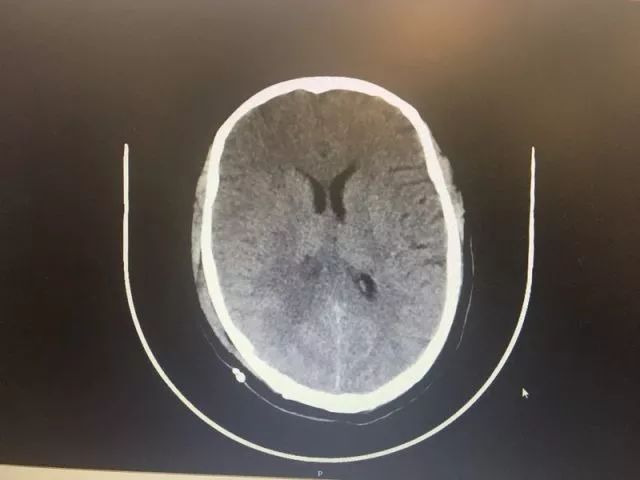

▲术前MR及CT

▲ 术后CT